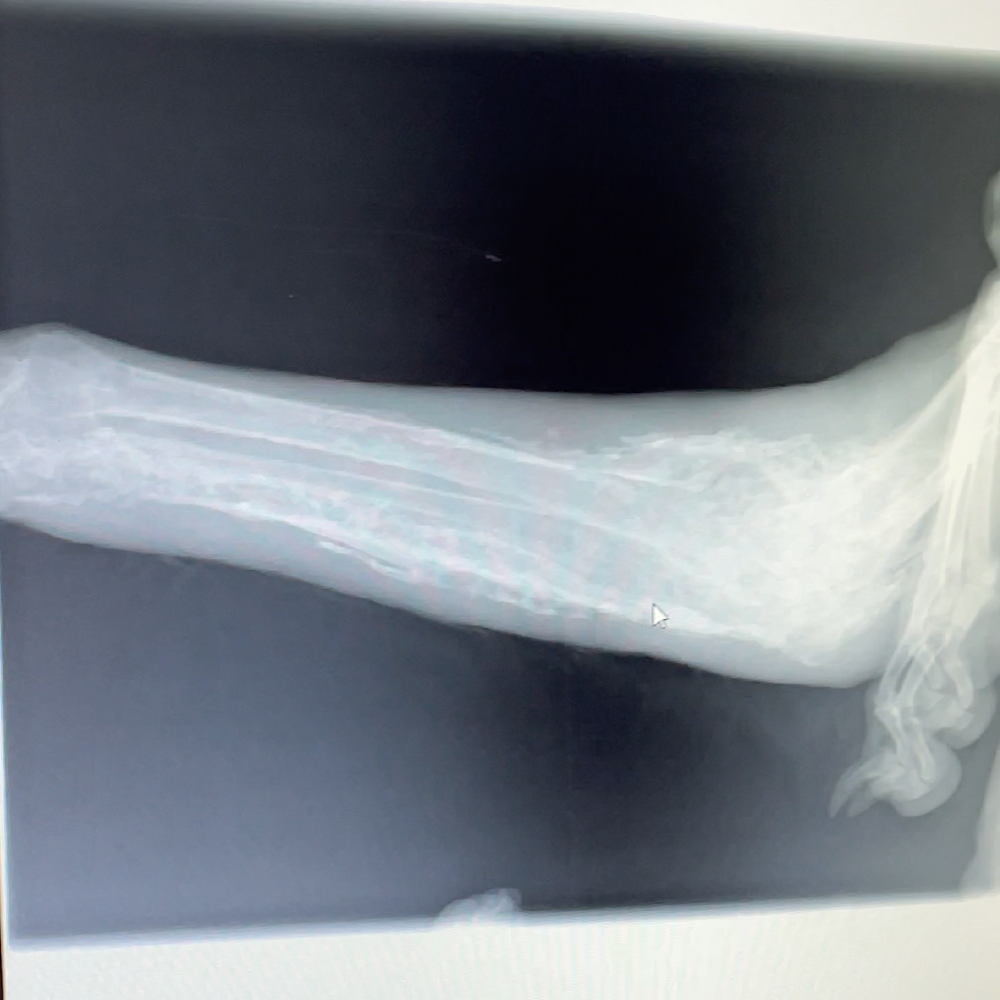

She was rushed to a clinic where a vet performed an X-ray on her swollen paw and discovered that she has cancer.

She needs her leg amputated to save her life and prevent the cancer from spreading. After surgery, she will also need months of nutritious food and rehab to regain her strength and walk again.